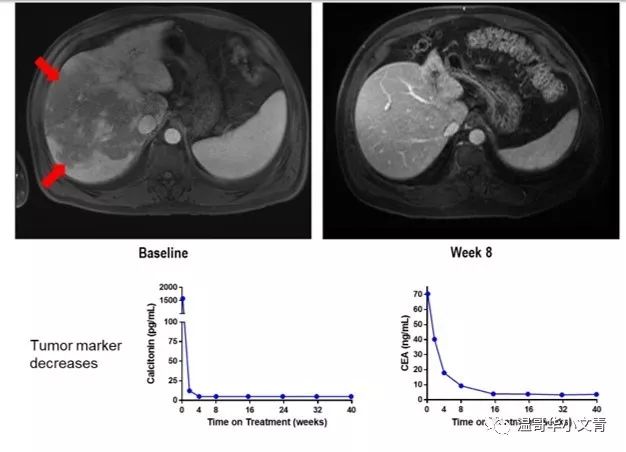

我们再来看看个体的情况。上图是一个57岁的遗传性髓样癌病人,服用了卡博替尼,凡德他尼,乐伐替尼三种靶向药后病灶仍然进展,左边箭头所指的位置就是肝脏巨大的转移灶。服用LOXO-292四周后,降钙素就从1500降低到检测不到;服用LOXO-292八周后肝脏的转移灶彻底消失。神不神奇?